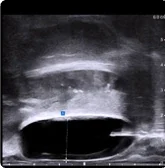

BioProtect 215cc Prostate

215 cc Prostate Post-MRI showing BioProtect Balloon Spacer, prostate, and rectum.

Post-MRI

Image courtesy of Dr. Shawn Zimberg, Radiation Oncologist.